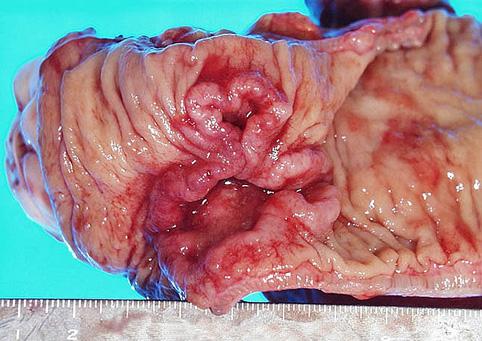

疾病(病理主体)的分类恶性上皮性肿瘤/腺癌

部位(按器官分)大肠/直肠

检查方法切除标本(宏观)

肿瘤的肉眼分类2型(溃疡局限型)/

肿瘤最大直径40以上

肿瘤的深度s(a)